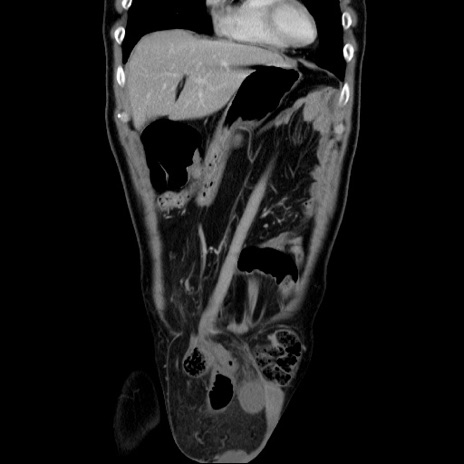

症例34(冠状断像)

【症例】60歳代 男性

【主訴】右鼠径部膨隆

【現病歴】1年程前より右鼠径部膨隆あり。自己にて還納可能だったため放置していた。3時間前より右鼠径部の脱出を認め、還納困難となり受診。

【既往歴】高血圧

【身体所見】右鼠径部に小児頭大の膨隆あり。弾性硬であり、用手還納は困難。左鼠径部にも膨隆を認める。脱出はなし。